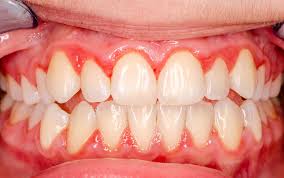

- Diş plakları ve tartar (diş taşı) birikimi, gingivitis ve periodontitise yol açar.

- Gingivitis: Sadece dişetinde inflamasyon vardır, başlangıç aşamasında genellikle çekilme görülmez.

- Periodontitis: Dişeti ve alveolar kemiğin kaybına yol açan ileri inflamasyon, diş eti çekilmesinin en yaygın biyolojik nedenidir.

- Periodontal cep oluşumu ve kemik kaybı, dişetinin diş kökü üzerinden geri çekilmesini kolaylaştırır.